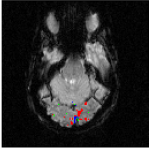

The Experience Based Cognition competition (EBC) (University of Pittsburgh, 2007) offers an opportunity to study complex responses to natural environments. The EBC datasets comprise three 20-minute runs (704 TRs in each run) of subjects interacting in an urban virtual reality environment. Subjects were audibly instructed to complete three search tasks in the environment: looking for weapons (but not tools) taking pictures of people with piercing (but not others), or picking up fruits (but not vegetables). The data was collected with a 3T EPI scanner (TR = s, xy dimension: , voxel size = mm, 34 slices with a thickness of mm). We analyze the second runs of subjects 14 and 13. For each subject, the matrix is composed of intra-cranial voxels at TRs. We first remove the non regionally specific variance captured by the first eigenmodes of a singular value decomposition of the dataset. We then compute using and . After embedding the dataset into four dimensions, we cluster the voxels. Figs. 18 and 20 display the datasets after embedding. Because we cannot display four dimensions, we show the projections of the dataset on three consecutive coordinates. All the coordinates contribute to the spread the dataset along elongated arms, which facilitates the clustering. Voxels that do not correspond to the background activity (the maroon cluster in Figs. 18 and 20) are superimposed on anatomically registered structural images and colored according to their cluster label (see Figs. 19 and 21). For both subjects, the clusters are connected regions (see Figs. 19 and 21), compactly organized around functional areas related to the processing of visual, and auditory stimuli (music, cellphone ringing, dog roaring) in the virtual environment. It is important to emphasize that our method never enforces any form of spatial proximity, and is purely based on functional connectivity.

For subject 14 (Fig. 19), the orange cluster corresponds to activation in the calcarine cortex associated with V1/V2 representations of the lower visual fields, while the light blue cluster corresponds to representations of the upper visual fields. Activation in lateral areas (visual motion areas, MT/V5) is also present, as well as activity in the posterior convexial cortex (area VP). The activation is predominantly in the right hemisphere. Interestingly, the two clusters located in the visual cortex (light blue and orange) have very similar and coordinates (see Fig. 18-left). The cyan cluster corresponds to activation in the right frontal gyrus (Broca area) associated with language comprehension. The yellow clusters are located in the right and left superior temporal gyri and medial temporal gyri (Wernicke area). These regions correlate with activation

in the auditory cortex and language areas. Finally, the dark blue cluster corresponds to activation in the prefrontal cortex. A very similar pattern of activity (Fig. 21) was obtained for subject 13. The blue and orange clusters, located in the calcarine cortex, correspond to V1 and V2 areas. Again, these two clusters, both located in the visual cortex, have similar and coordinates. The green cluster is located in the medial temporal gyrus (Wernicke area) and is associated with language processing.